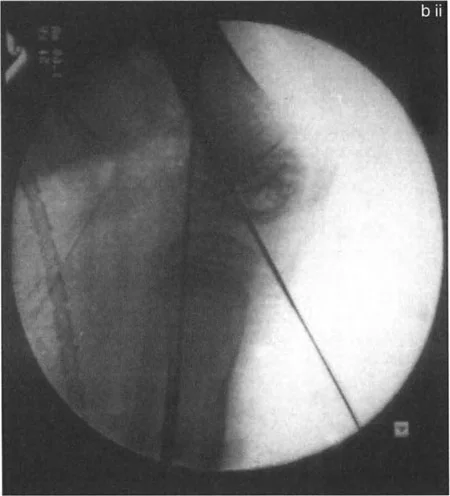

تتضمن جراحة قطع العظم قطع العظم (عادة عظم الفخذ أو الساق) وإعادة تشكيله لتغيير محاذاة المفصل. يمكن أن يكون القطع:

- قطع العظم بالوتد المفتوح (Opening Wedge Osteotomy): يتم عمل قطع في العظم ثم فتح فجوة صغيرة تُملأ غالبًا بطعم عظمي، مما يطيل الجزء المعني من العظم ويصحح المحاذاة.

- قطع العظم بالوتد المغلق (Closing Wedge Osteotomy): يتم إزالة جزء صغير من العظم على شكل وتد، ثم تُغلق الفجوة وتُثبت العظام، مما يقصر الجزء المعني ويصحح المحاذاة.

يتم تثبيت العظام بعد القطع باستخدام صفائح ومسامير أو تثبيت خارجي، لضمان التئام العظم في الوضعية الجديدة.

- مخاطر العصب الشظوي: التصحيح الحاد للانحراف الأروح في الساق قد يؤدي إلى شد العصب الشظوي، مما قد يسبب إصابة العصب أو متلازمة الحيز. قد يُنصح بإجراء تحرير وقائي للعصب الشظوي وقطع اللفافة (Fasciotomy) في التصحيحات الكبيرة، أو استخدام التصحيح التدريجي بالتثبيت الخارجي.

- التصحيح التدريجي: في حالات تحدد الحركة الشديدة أو المعقدة، قد يكون التصحيح التدريجي باستخدام التثبيت الخارجي هو الخيار الأكثر أمانًا.

اعتبارات جراحية إضافية